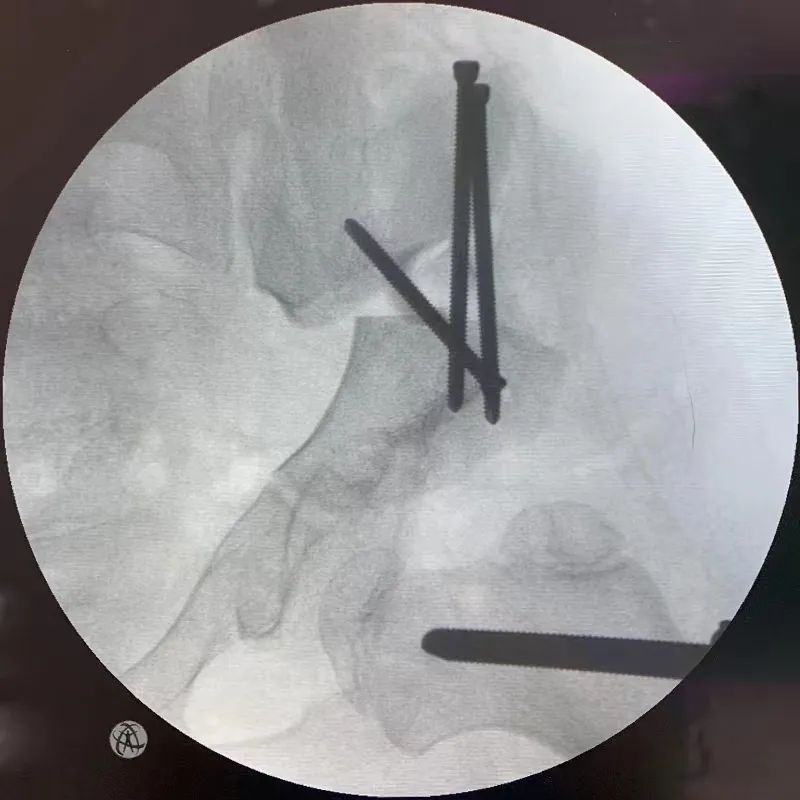

入院后完善相关检查,主任医师杜香平团队针对女童的病情进行详细讨论,为其制订了骨盆三联截骨术方案。杜香平介绍,骨盆三联截骨是目前治疗大龄儿童髋关节脱位相对有效的方法,但需要同时切断髂骨、耻骨及坐骨,其技术难度高,操作复杂,稍有不慎易损伤神经(坐骨神经、闭孔神经)和血管(存在号称死亡之冠的血管),因此手术难度对于医生来说是个不小的挑战。

经团队充分、细致的术前准备,杜香平团队,在麻醉科手术室的密切配合下进行手术。经过严密的手术操作,女童的髋臼产生足够的旋转,较充分的矫正了畸形。旋转后的髋臼中心不外移,术后步态影响较少,明显增加了女童的髋臼透明软骨承重面积。